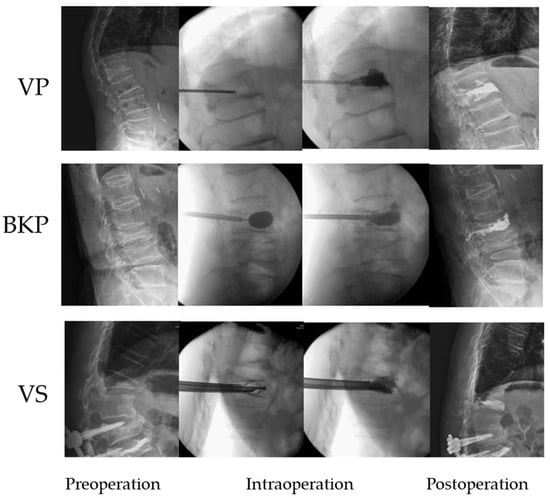

2.2.1. Establishment of VP Model in T12 Compression Fracture

2.2.2. Establishment of BKP Model in T12 Compression Fracture

2.2.3. Establishment of VS Model with Bone Cement Augmentation in T12 Compression Fracture